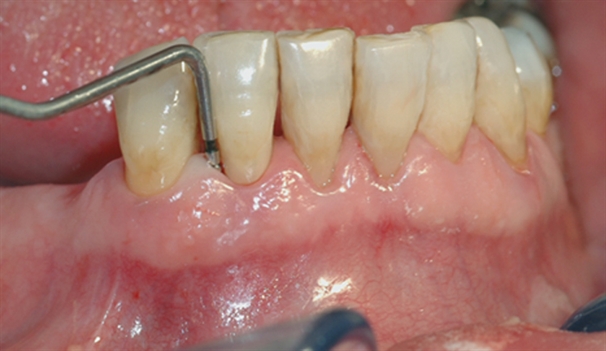

En undersøkelse med lommeregistrering avdekker likevel et omfattende bentap ved den ene tannen.

Instrumentet er her lagt utenfor tannkjøttet for å vise hvor stort festetapet egentlig er.